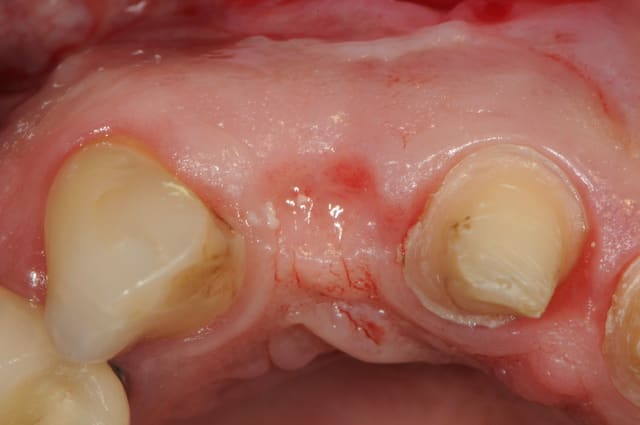

bon, je donne la réponse:

12 à 22 sont effectivement des couronnes:

-22 à été posée juste avant que je ne vois la patiente pour un problème récurent d'infection chronique sur 22.

je fais donc une résection apicale sur 22, mais manque de bol il y a récidive et le traitement échoue.

on décide donc d'extraire 22 tout en refaisant un bridge sur 11 et 21 avec un cantilever pour la 22 nouvellement extraite.

je dis à la patiente que la pose d'in implant n'est pas forcément ce qu'il y a de mieux et qu'il vaut mieux attendre la cicatrisation pour décider...

deux mois après (photo 2-3-4), l'état de la gencive me paraît plutôt sympa et je propose donc d'en rester là. toutefois la patiente ne veut pas, elle à peur de perdre le bridge (même le définitif) , bref, elle veut un implant !